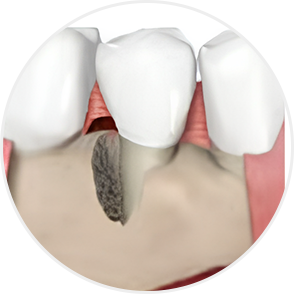

Even when severe periodontal disease has caused gingival recession and alveolar bone resorption, teeth can often be preserved through gum regeneration therapy using Emdogain. This procedure regenerates damaged alveolar bone and surrounding periodontal tissue. By applying Emdogain — a specialized gel that stimulates periodontal tissue regeneration — the supporting structures of the tooth are rebuilt, allowing function and health to be restored without extraction.

Supports regeneration of alveolar bone damaged by chronic periodontitis

Restores periodontal tissue, alveolar bone, and periodontal ligament around teeth

Acts deep within the periodontal tissues to support regeneration of the gingiva, periodontal ligament, and alveolar bone around the tooth root.